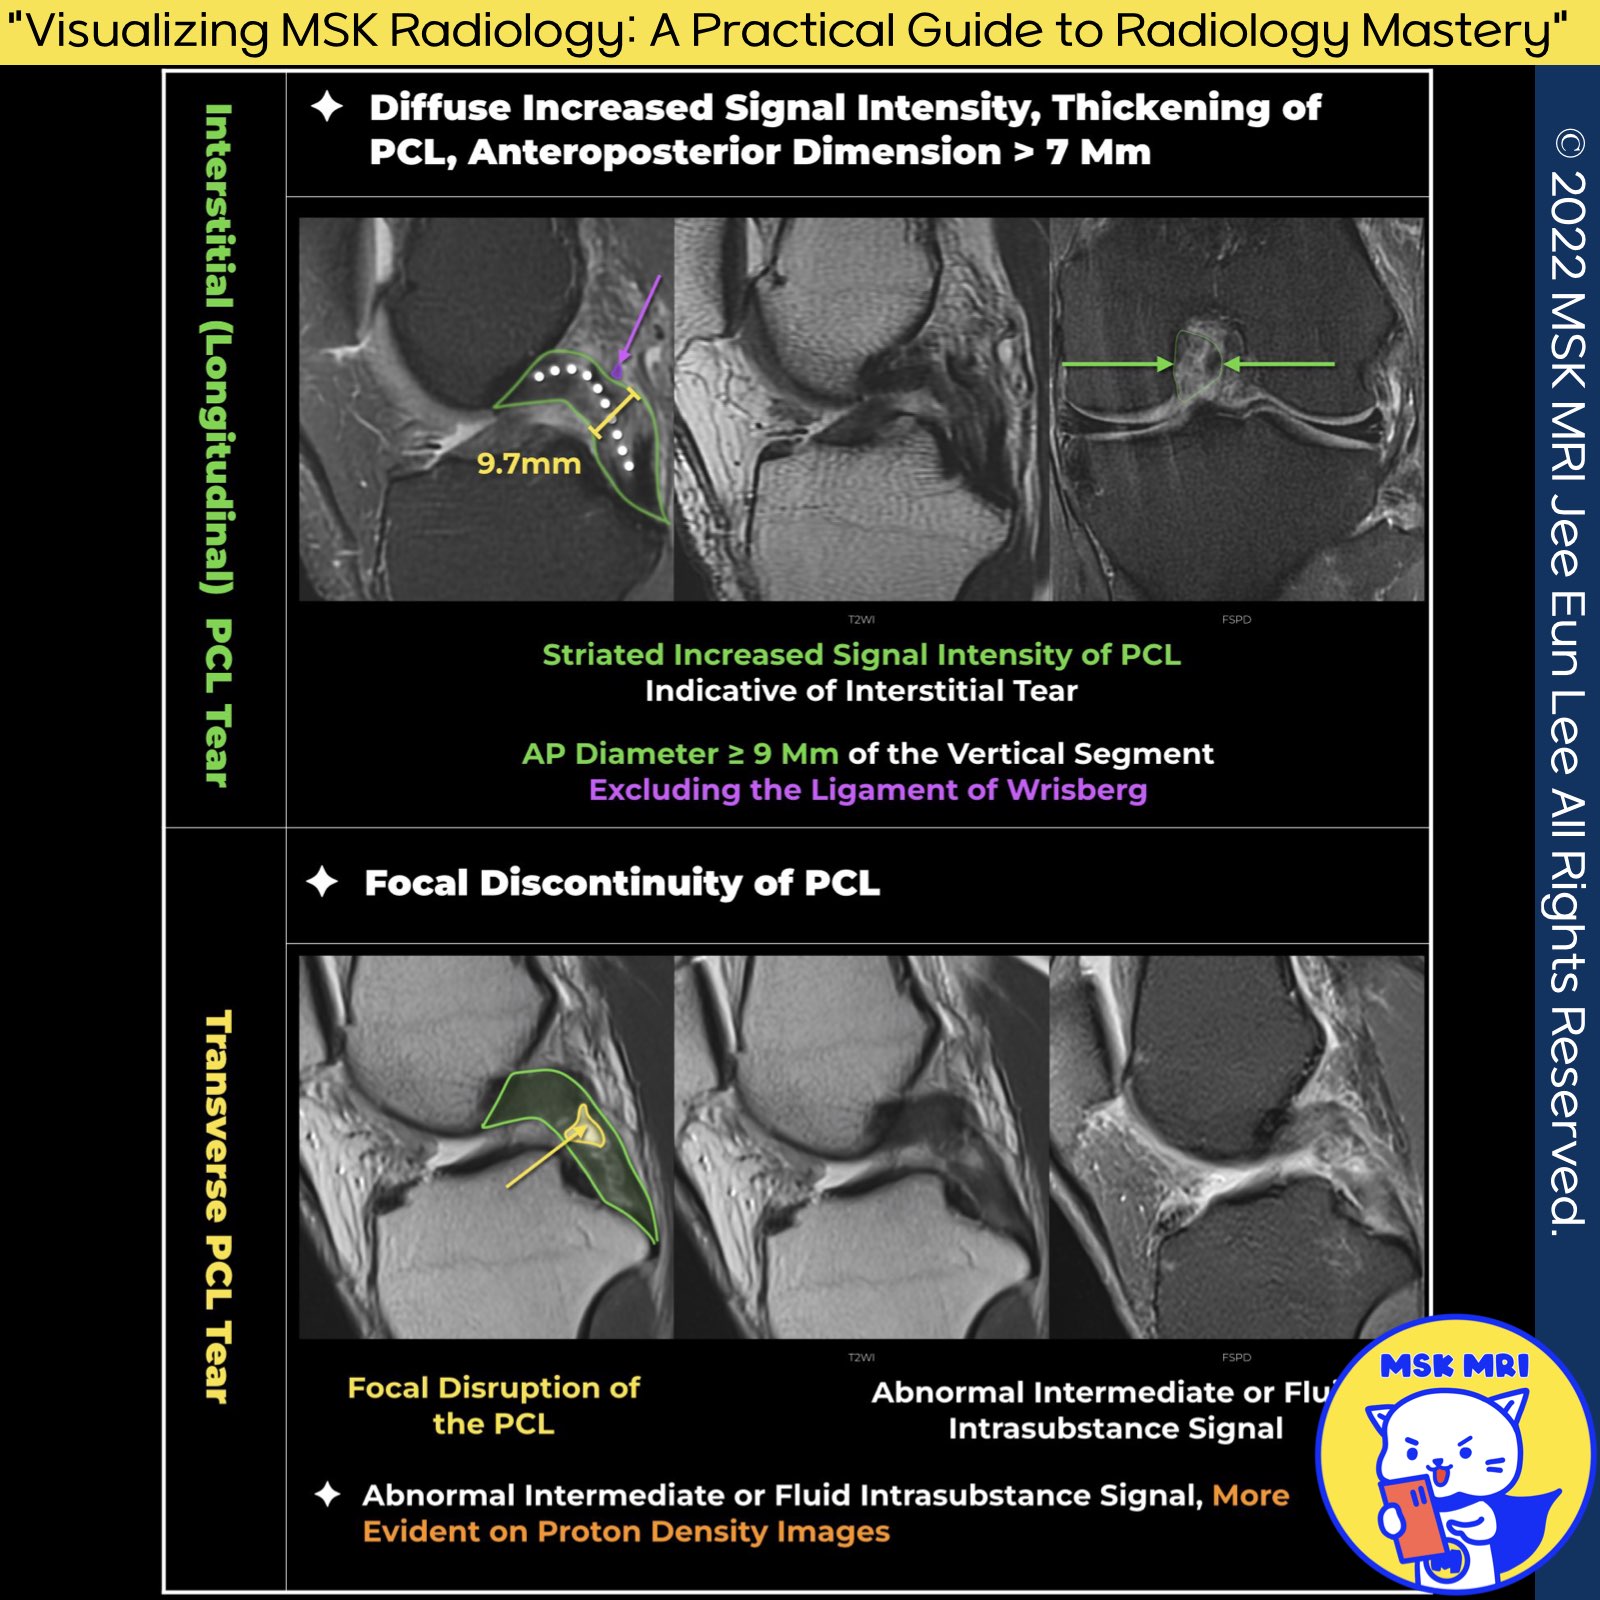

1️⃣ MRI Signs of PCL Tear:

- Focal disruption of the PCL.

- Amorphous increased signal intensity with disruption of one or both margins of the ligament.

- Increased signal intensity on proton density images is more common than on T2-weighted images.

- Nonvisualization of the PCL.

- Abnormal thickening of the PCL distal to the genu with an anteroposterior diameter of greater than 7 mm. (Magn Reson Imaging Clin N Am. 2014 Nov;22(4):557-80.)

2️⃣ PCL Injury Patterns:

- Injury to the PCL may result in transverse or longitudinal interstitial tears. (Radiology. 2016 Oct;281(1):23-40)

✅ Interstitial Tears: The anteroposterior diameter of the ligament distal to the genu is greater than 7 mm on a sagittal T2-weighted sequence.

✅ Transverse Tears: Focal disruption of the PCL.